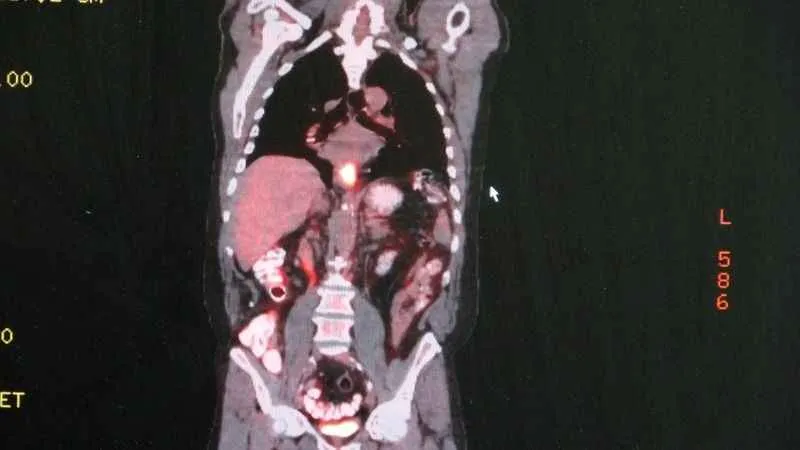

Yemek borusu kanserine dikkatDünyada en sık görülen kanser türleri arasında 9. sırada olan yemek borusu kanseri hakkında uyarılarda bulunan Marmara Üniversitesi Pendik Eğitim ve Araştırma Hastanesi Göğüs Cerrahisi Anabilim Dalı Doktor Öğretim Üyesi Nezih Onur Ermerak, "Yemek borusu kanseri geç bulgu ve şikayet verdiği için hastalar erken evrede fark edemezler. Hastaların sadece yüzde 25'ini diğer organlara sıçramadan yakalayabiliyoruz" dedi.

Artan yemek borusu kanseri vakalarının ardından hastalıkla alakalı uyarılarda bulunan Ermerak, "Yemek borusu kanseri dünyada 9. sırada en sık görülen kanser tipidir. Ve çok sinsi seyreden bir hastalıktır. Geç bulgu ve şikayet verdiği için genelde hastalar erken evrede fark edemezler. Hastaların sadece yüzde 25'ini diğer organlara sıçramadan yakalayabiliyoruz. Hastalar bu kansere erken evrede yakalandıklarında sağ kalımları yükseliyor. Bu hastalığın semptomları; yutma güçlüğü, yemek yerken takılma hissi, istemsiz kilo kaybı, öksürük, göğüs, iman tahtası ve sırtta özellikle yemek sonrası gelen bir ağrı ve bu gibi şikayetlerle hastalar mutlaka ilgili merkeze başvurmalılar. Erken evrede teşhis hastaların tedavi şansı artmaktadır." dedi.